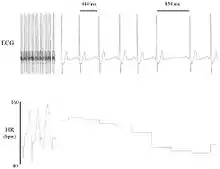

Heart rate variability (HRV) is the physiological phenomenon of variation in the time interval between heartbeats. It is measured by the variation in the beat-to-beat interval.

Other terms used include: "cycle length variability", "R–R variability" (where R is a point corresponding to the peak of the QRS complex of the ECG wave; and RR is the interval between successive Rs), and "heart period variability".

Methods used to detect beats include: ECG, blood pressure, ballistocardiograms,[1][2] and the pulse wave signal derived from a photoplethysmograph (PPG). ECG is considered the gold standard for HRV measurement[3] because it provides a direct reflection of cardiac electric activity.[4]